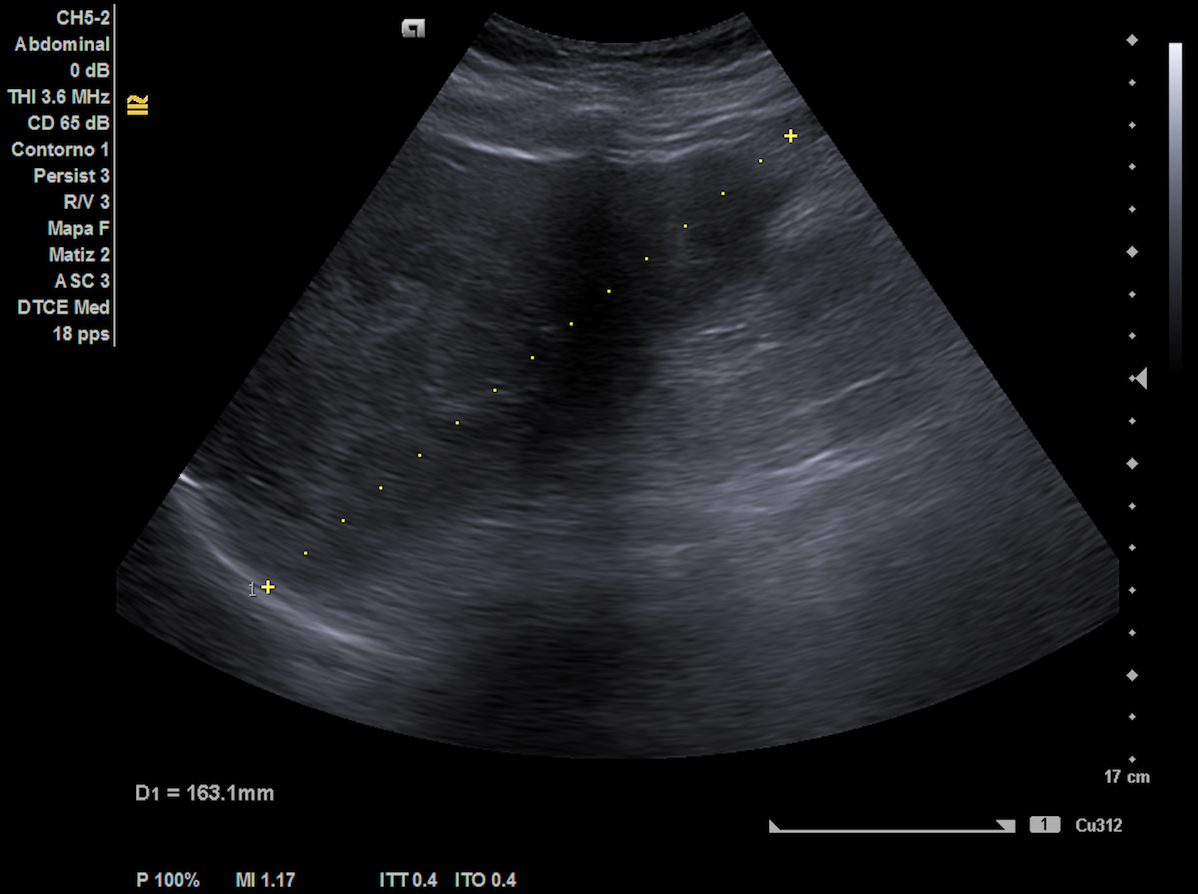

Ecografía hepática: hígado de tamaño normal con ecoestructura heterogénea, lesiones focales con halo hipoecoico en ambos lóbulos, sugerentes de metástasis. Las imágenes ecográficas del ingreso coincidían con nuestra descripción.